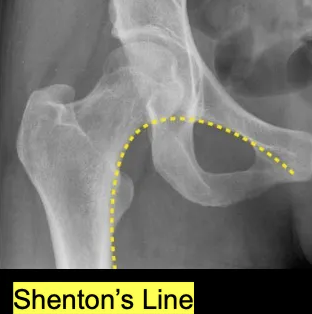

Q

What is the most important line to observe in hip XR?

A

Shenton’s line